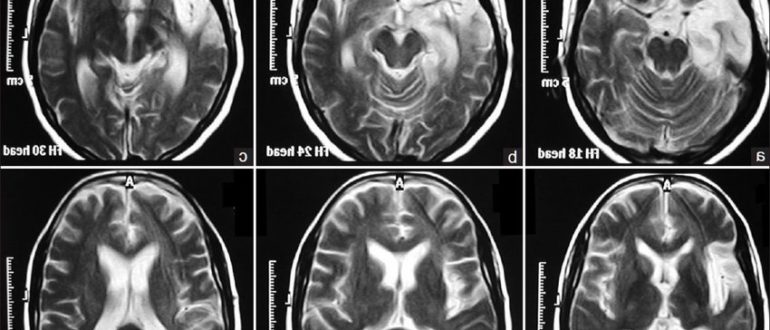

Дисциркуляторная энцефалопатия на МРТ головного мозга

Проведение МРТ при дисциркуляторной энцефалопатии мозга Дисциркуляторная энцефалопатия головного мозга — прогрессирующее заболевание хронического характера, которое вызвано повреждением сосудов и нарушением мозгового кровообращения. Мозг отвечает за правильное функционирование…